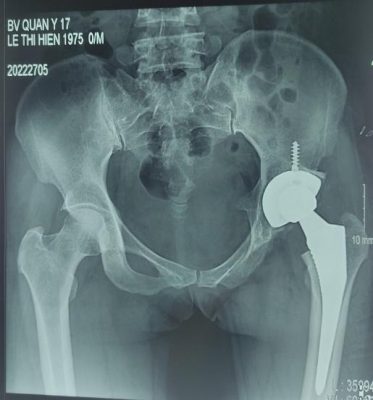

Gãy cổ xương đùi di lệch Thay khớp háng toàn phần điều trị gãy cổ xương đùi di lệch

- Chấn thương khớp háng: gãy cổ xương đùi di lệch ở bệnh nhân cao tuổi; gãy nhiều mảnh chỏm xương đùi; gãy liên mấu chuyển mất vững ở bệnh nhân cao tuổi, loãng xương nặng mà trước đó chức năng khớp còn tốt.